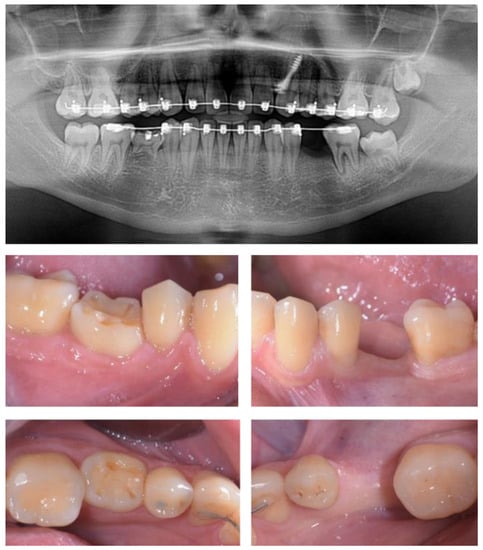

2.2. Patient Characteristics

2.3. Treatment Procedure

2.5. Individual Cases Description

- Case 1:

- Case 2:

- Case 3:

- Case 4:

- Case 5: